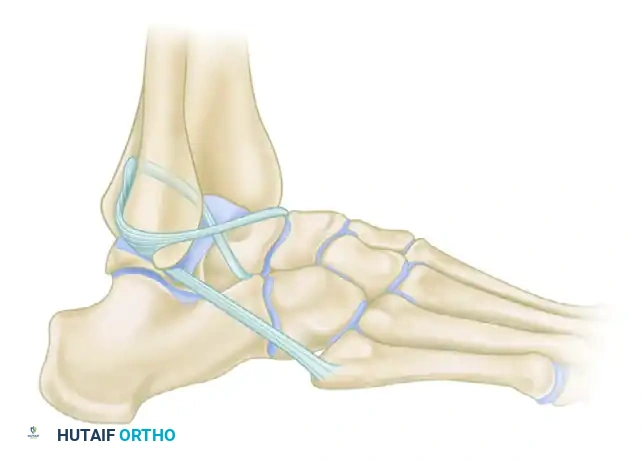

Comparative Note: The Evans Technique

While the Watson-Jones technique routes the tendon through both the fibula and the talus, other historical non-anatomic tenodeses exist. For instance, the Evans technique (shown below for comparative anatomical context) routes the peroneus brevis solely through a single fibular tunnel from anterior to posterior, primarily addressing the ATFL vector but offering less rotational control than the Watson-Jones or Chrisman-Snook procedures.

FIGURE 89-26 B: Evans technique. Note the simpler routing through a single fibular tunnel, contrasting with the dual-tunnel Watson-Jones approach.